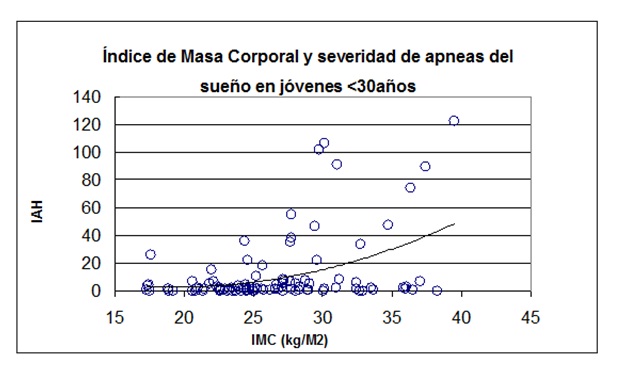

El peso corporal aumentado fue un hallazgo frecuente (promedio 95.5 ± 24.5 kg). Resultó en un índice de masa corporal (IMC) promedio de 34,6 ± 8,1 kg/m2. Se analizó a la obesidad como factor de riesgo predictor de la severidad de las apneas del sueño. Se excluyó de este análisis a los pacientes con IMC > de 40 Kg/m2, para no incluir a los pacientes con síndrome de hipoventilación-obesidad. Existió una correlación significativa, aunque con importante dispersión de valores, entre el índice de masa corporal y el índice de apneas-hipopneas por hora de sueño (r2 = 21,1%, p < 0.001). En pacientes menores de 30 años esta correlación se mantuvo (r2 = 21,9%, p < 0.0004) (Figura 8) (Figura 9).

Figura 8: En pacientes adultos, relación entre el índice de masa corporal yel índice apneas + hipopneas del sueño.

La obesidad fue el factor de riesgo más asociado a la severidad de las apneas del sueño. Los valores de IMC son particularmente elevados, superiores a otras series y en concordancia con la prevalencia de obesidad en nuestro país. Es especialmente destacable el hallazgo de jóvenes con grados severos de obesidad, esperable de acuerdo a los datos de las encuestas nacionales30 y de otros países31.